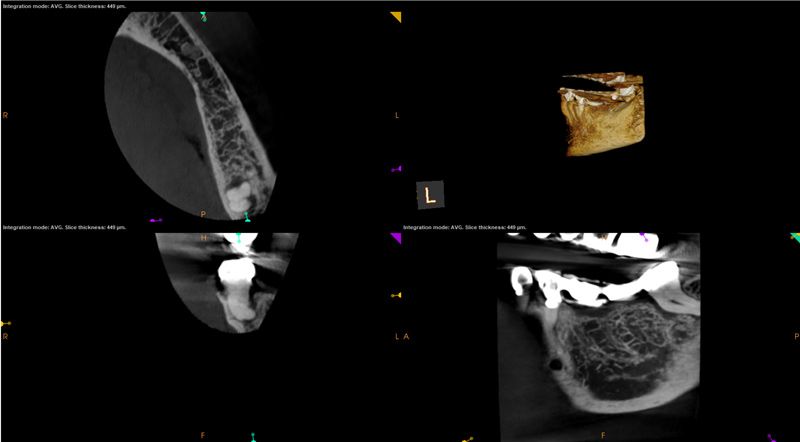

The second case study is that of a healthy 88-year-old woman who presented with significant bone loss on the mesial and apical aspect of tooth No. 18, which would suggest potentially a vertical fracture in the tooth (Figure 9 and Figure 10). The clinician had initially recommended extraction, which they informed the patient would likely be the best course of action, especially given that she had plenty of bone anterior to the tooth to place implants. When the recommendation of extraction was made to the referring dentist, he had some resistance because both he and the patient were interested in saving the tooth. Although the clinician initially stood firm on the recommendation, he received a call from the general dentist about a month later. He further expressed their desire to save the tooth, and he asked if the endodontist thought the new technology, the GentleWave Procedure, could be a solution. The informed consent was obtained and the patient was scheduled for treatment. Because the canal was quite calcified apically, a defined working length could not be determined. Obturation was performed using warm vertical condensation of gutta-percha.

As indicated in Figure 11, the mesial aspect of the distal canal was never touched by instruments, yet he was able to clean, evidenced by the postoperative image. In the past, a case with this level of difficulty would have required at least two appointments, with an interim medication of calcium hydroxide, but the case was treated in a single-visit appointment.  As observed 7 months later (Figure 12), the patient returned completely asymptomatic, and complete bone healing had occurred that exceeded initial expectations.

Fig 9. Case 2: Significant bone loss on the mesial and apical aspect suggested a potential vertical fracture (Fig 9 and Fig 10). Radiographic images were taken immediately postoperatively (Fig 11) and 7 months postoperatively (Fig 12).

Fig 10. Case 2: Significant bone loss on the mesial and apical aspect suggested a potential vertical fracture (Fig 9 and Fig 10). Radiographic images were taken immediately postoperatively (Fig 11) and 7 months postoperatively (Fig 12).

Fig 11. Case 2: Significant bone loss on the mesial and apical aspect suggested a potential vertical fracture (Fig 9 and Fig 10). Radiographic images were taken immediately postoperatively (Fig 11) and 7 months postoperatively (Fig 12).

Fig 12. Case 2: Significant bone loss on the mesial and apical aspect suggested a potential vertical fracture (Fig 9 and Fig 10). Radiographic images were taken immediately postoperatively (Fig 11) and 7 months postoperatively (Fig 12).